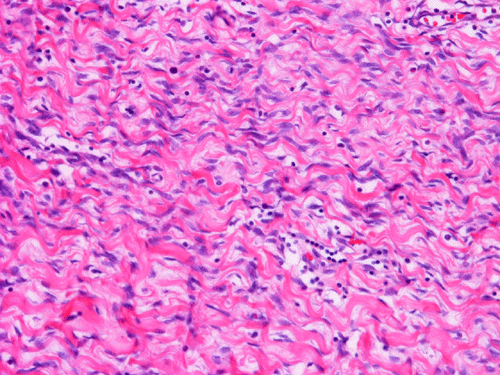

The excised mass is composed of an intermingled arrangement of mature adipose tissue, densely packed primitive spindle cells with small amount of cytoplasm, and mature appearing spindle cells with substantial amount of cytoplasm that gives the appearance of smooth muscle (Panel  A). Abrupt transition between the three elements are common (Panel B). The densely packed, small primitive spindle cells have elongated, cigar-shaped nuclei with amphophilic cytoplasm. Pleomorphism and mitotic figures are not seen. A small number of lymphocytes are present among these cells (Panel C). In areas with appeance of smooth muscle, the cells have elongated, sometime wavy nuclei without significant pleomorphism or mitosis (Panel D). Areas with thick, wavy collagen fibers admixed with benign appearing spindle cells are also present (Panel E and F) and some of these areas are more loosely packed than the other areas which may mimic the appearance of a neurofibroma. In contrast to other areas, these collagenous areas merge imperceptibly with the more cellular areas. In some of the densely packed spindle cell areas, there are small packets of loosely packed cells that give a myxomatous morphology on high magnification (Panel G and H).